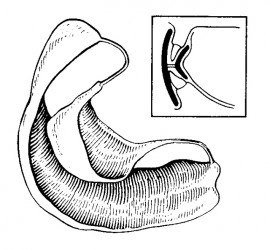

Характеризуя состояние слизистой оболочки протезного поля, Суппли выделяет четыре класса: Здоровая слизистая оболочка полости рта (умеренно податливая, умеренно подвижная, бледно–розового цвета). Атрофичная слизистая оболочка полости рта (малоподатливая, бледно–розового цвета, слабо увлажнена, с повышенной болевой чувствительностью); Слизистая оболочка с избыточной податливостью, чрезмерно увлажнена; Чрезмерно подвижная слизистая оболочка, расположена в области вершины […]